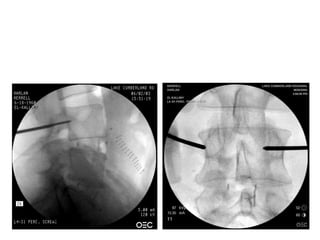

Transpedicular

Oblique View

Biopsy

Drill and Curette